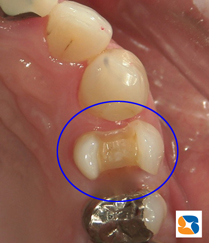

オールセラミックの詰め物 オールセラミックの白い詰め物

11月末。30代の女性。主訴は「犬歯の横の詰め物が取れた」でした。患者様にはセラミックの詰め物の強度、無変色、虫歯になりにくい長所をご理解して頂いたうえで、白いセラミックの詰め物を選択されました。